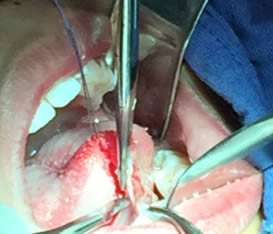

• Se pasa una sutura sin anudar en la punta de la lengua para traccionar la misma y facilitar las maniobras quirúrgicas. Posteriormente se utilizan dos pinzas de mosco, una curva y una recta pinzando el frenillo en su borde superior e inferior para limitar sus bordes. Figuras 3 y 4.

Figura 3. Sutura sin anudar en punta de la lengua

Figura 4. Pinzado del frenillo